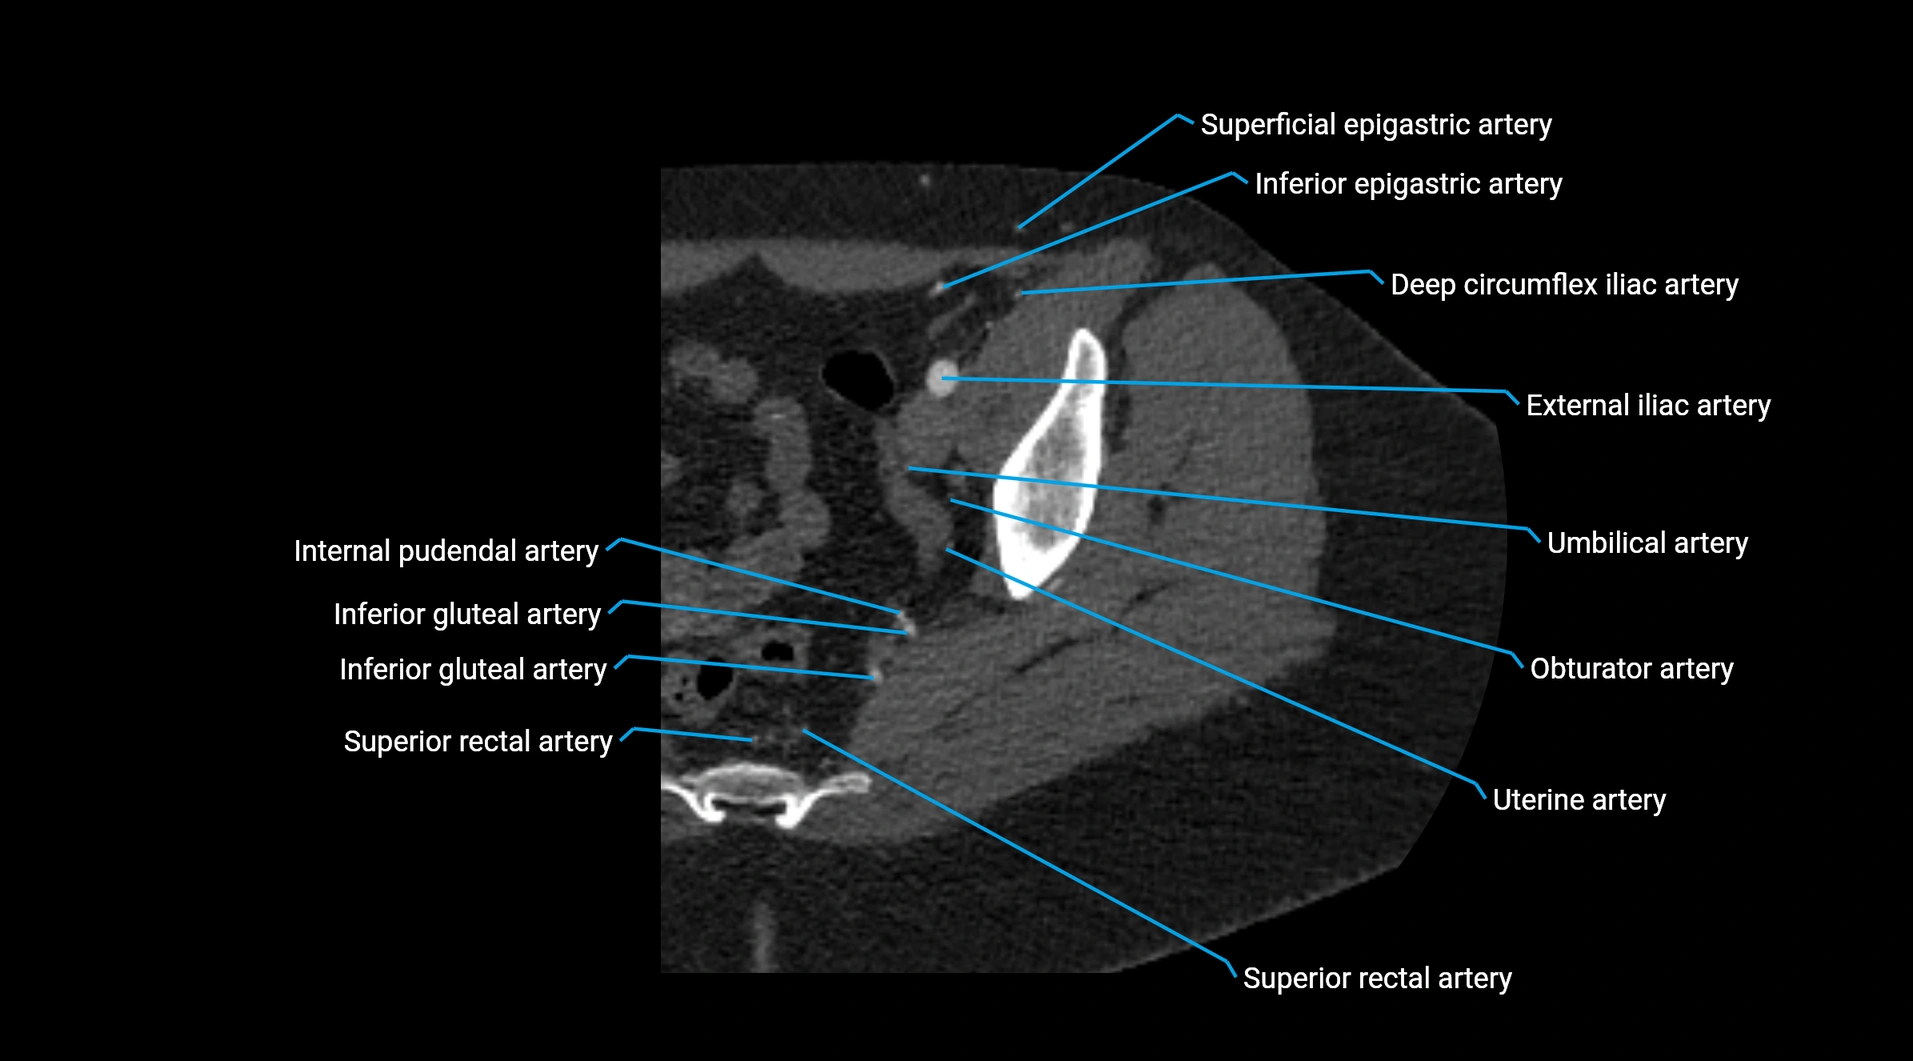

Contrast-enhanced CT (CTA):

• Gold standard for abdominal aortic imaging

• Provides excellent detail of lumen, wall, aneurysm, thrombus, and branch vessels

• Multiplanar and 3D reconstructions help in aneurysm measurement, stent graft planning, and dissection evaluation

• Detects acute rupture, traumatic injury, or occlusion with high sensitivity